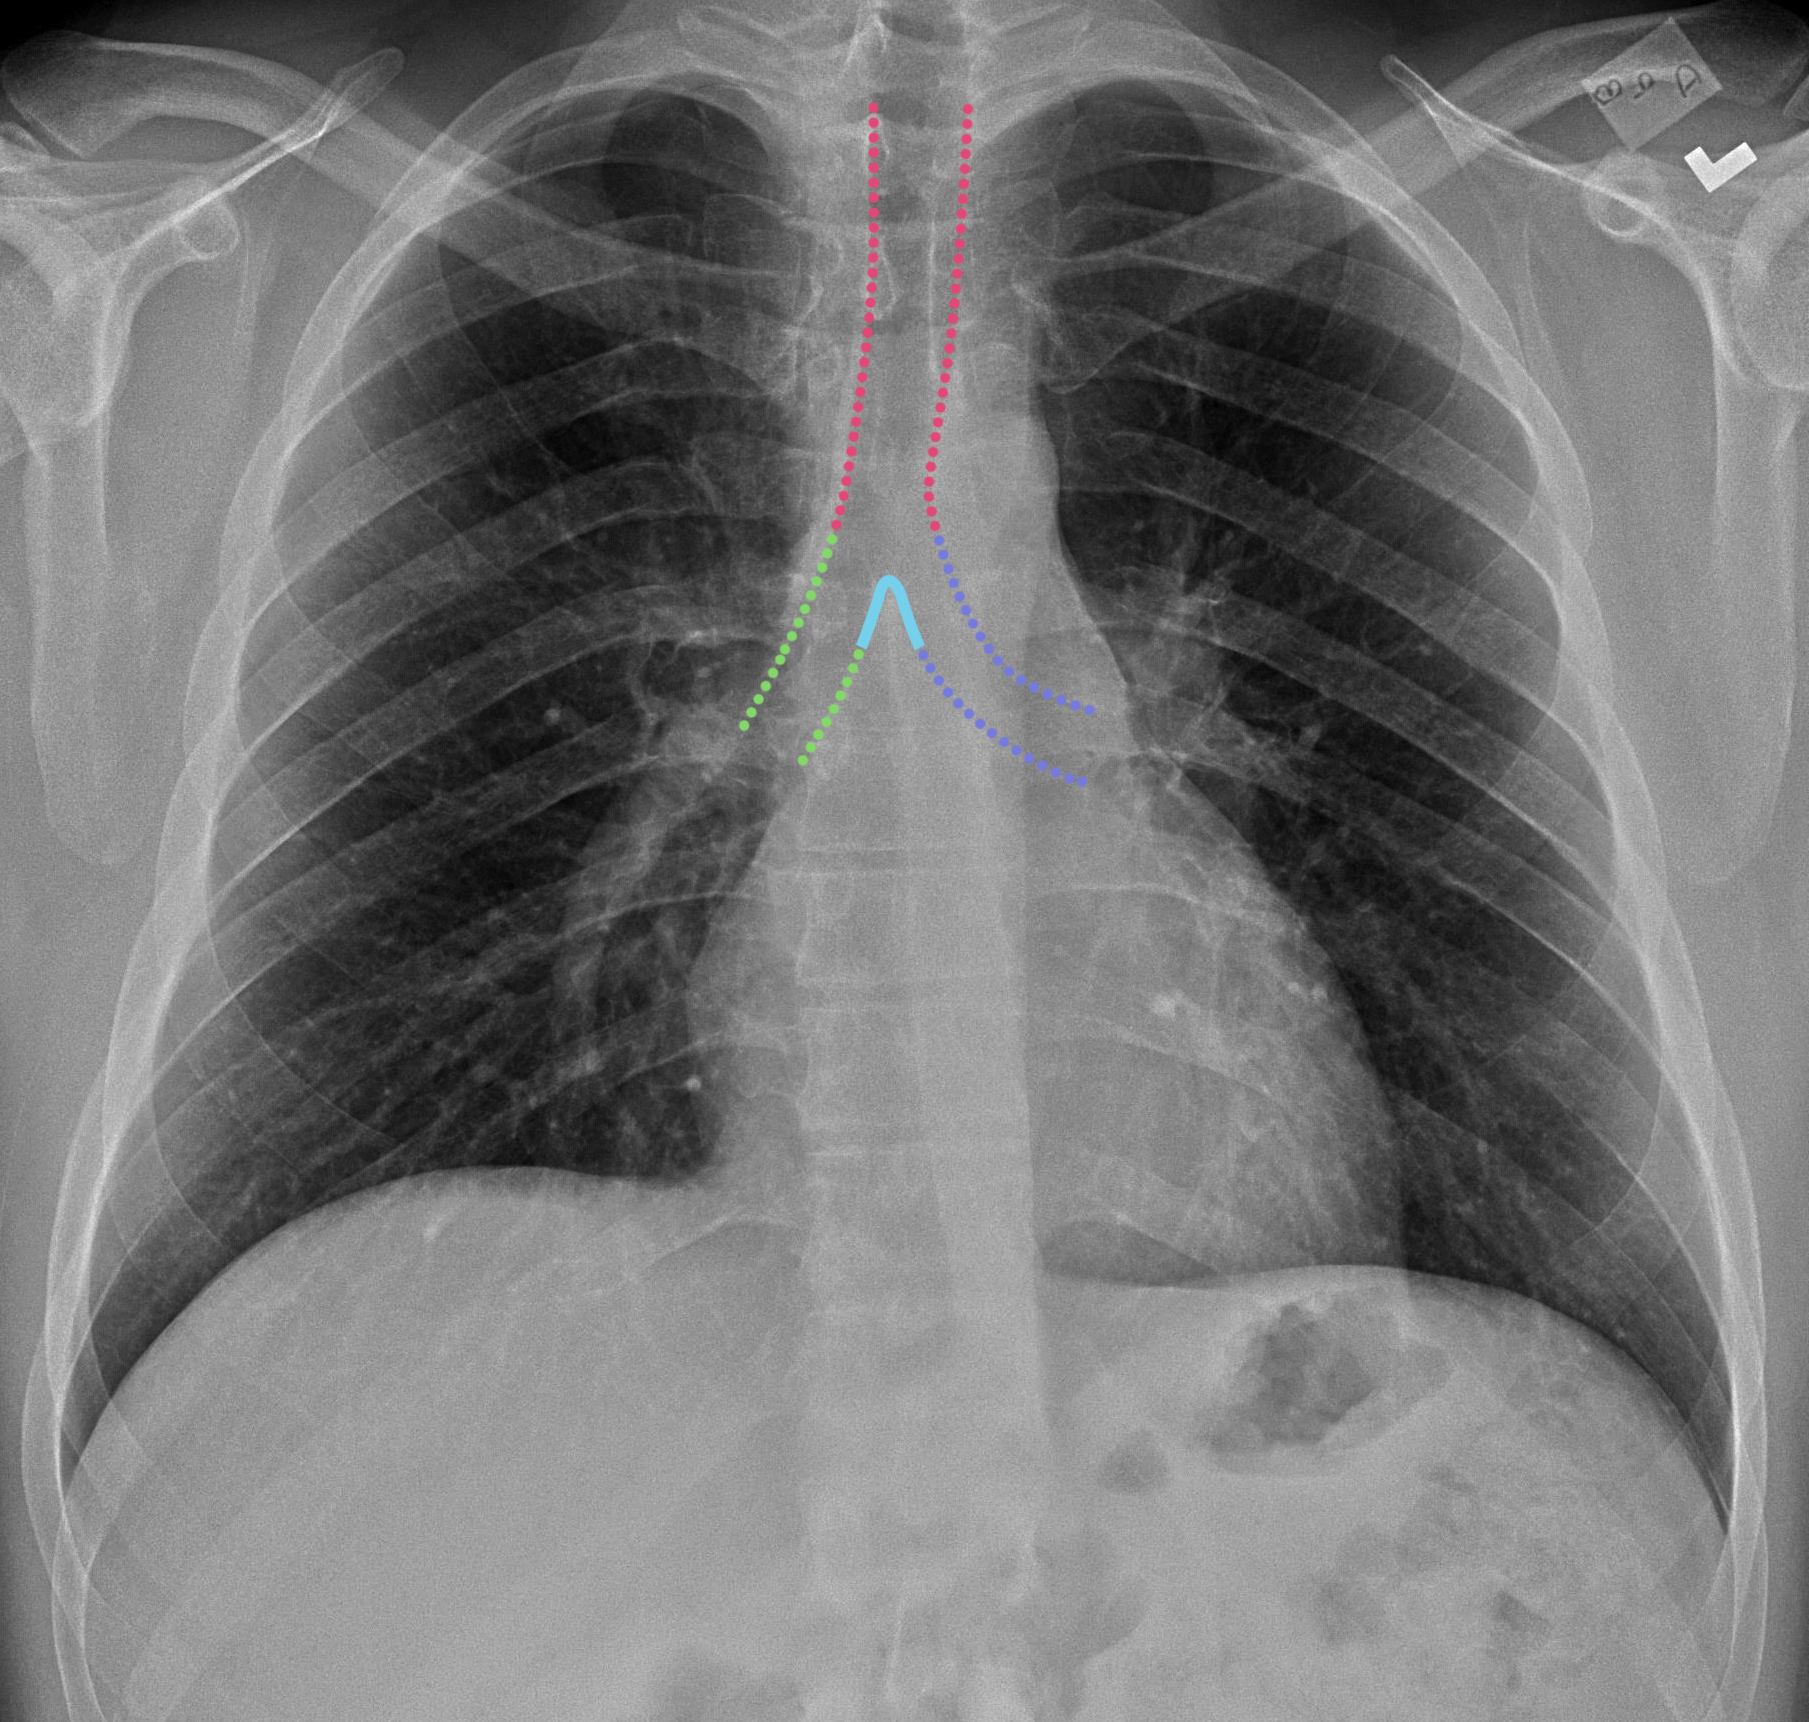

The interpretation of a chest film requires the understanding of basic principles. In fact every radiologst should be an expert in chest film reading. It first appears too complicated to read the chest xrays because we barely know what. It is almost always the first imaging study ordered to evaluate for pathologies of the thorax, although further diagnostic imaging, laboratory tests. Heart abnormalities, including fluid around the heart (pericardial effusion), an enlarged heart (cardiomegaly), heart failure, or abnormal anatomy of the heart can be. Therefore, knowing the basics and pathologies in the ed setting is very important. Common symptoms that can be diagnosed using chest. Labeled chest radiographs teaching radiologic anatomy with a level of detail appropriate for medical students.

Evaluation of a chest radiograph may appear to be simple, but is in fact a complex task requiring careful observation, sound understanding of chest anatomy, and knowledge of the principles of physiology and pathology.

Look for lung and pleural pathology. In this article we will focus on: Published 2011 by blackwell publishing ltd. It is used to evaluate the lungs, heart and chest what are the limitations of chest radiography? There are also important structures that are obscured or become visible. Heart abnormalities, including fluid around the heart (pericardial effusion), an enlarged heart (cardiomegaly), heart failure, or abnormal anatomy of the heart can be. Living anatomy of the chest for 1st year medical students original version compiled by dr. Evaluation of a chest radiograph may appear to be simple, but is in fact a complex task requiring careful observation, sound understanding of chest anatomy, and knowledge of the principles of physiology and pathology. Air spaces normally seen in. Gillian lieberman forthe harvard 62. Each of these anatomical structures should be viewed using a systematic approach. In fact every radiologist and pulmonary physician should be an expert in chest film reading. However, finding problems that are often a/w arrhythmias, such as cardiac enlargement and lung disease, should alter one to the possibility of arrhythmias.